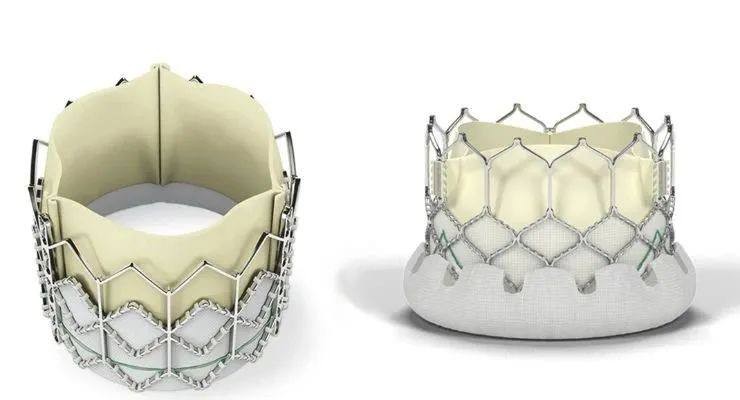

SAPIEN 3 Ultra RESILIA|爱德华生命科学

项目类型

器械质押区

起投金额

4000USDT

每日释放:0.85

释放周期:85 天

已购: 20000

剩余: 0